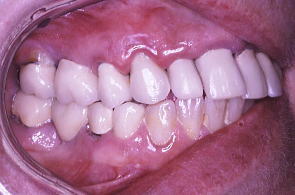

初診時の口の中の状態、歯ぐきは赤く腫れている。特に上の歯肉全体が浮腫して歯肉の締まりがなくなっている。